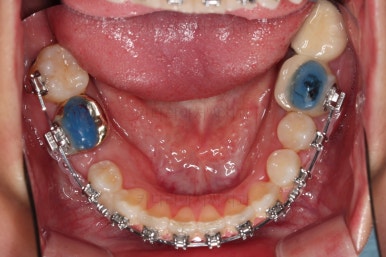

부산치과교정 키다리아저씨치과 초진 시 입안의 모습입니다.

확연히 좌우의 삐뚤어진 정도가 차이나죠.

덧니도 좌측(사진에서 보면 오른쪽) 위아래만 있는 상태고요.

좌측으로 삐뚤어져서 앞니도 좌측으로 쏠려 있는 상태였습니다.